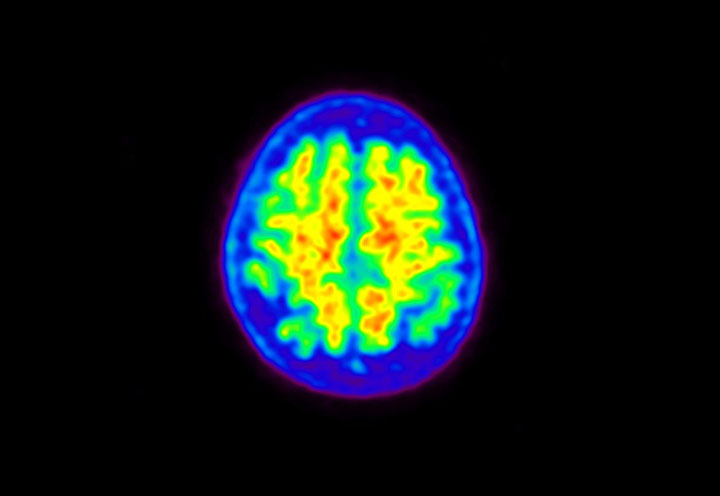

Head / Case5 : Amyloid

Courtesy : Kindai University Hospital

- Imaging protocol

- Injected dose: 4.27 MBq/kg, 18F-Flutemetamol

- Uptake time: 99 minutes

- Scan time: 20 minutes